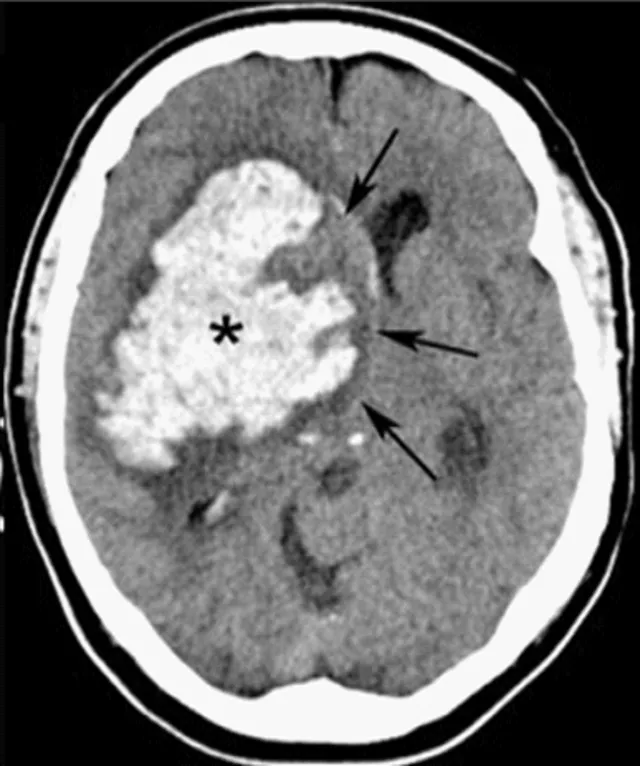

- Stroke (ischemic & hemorrhagic).